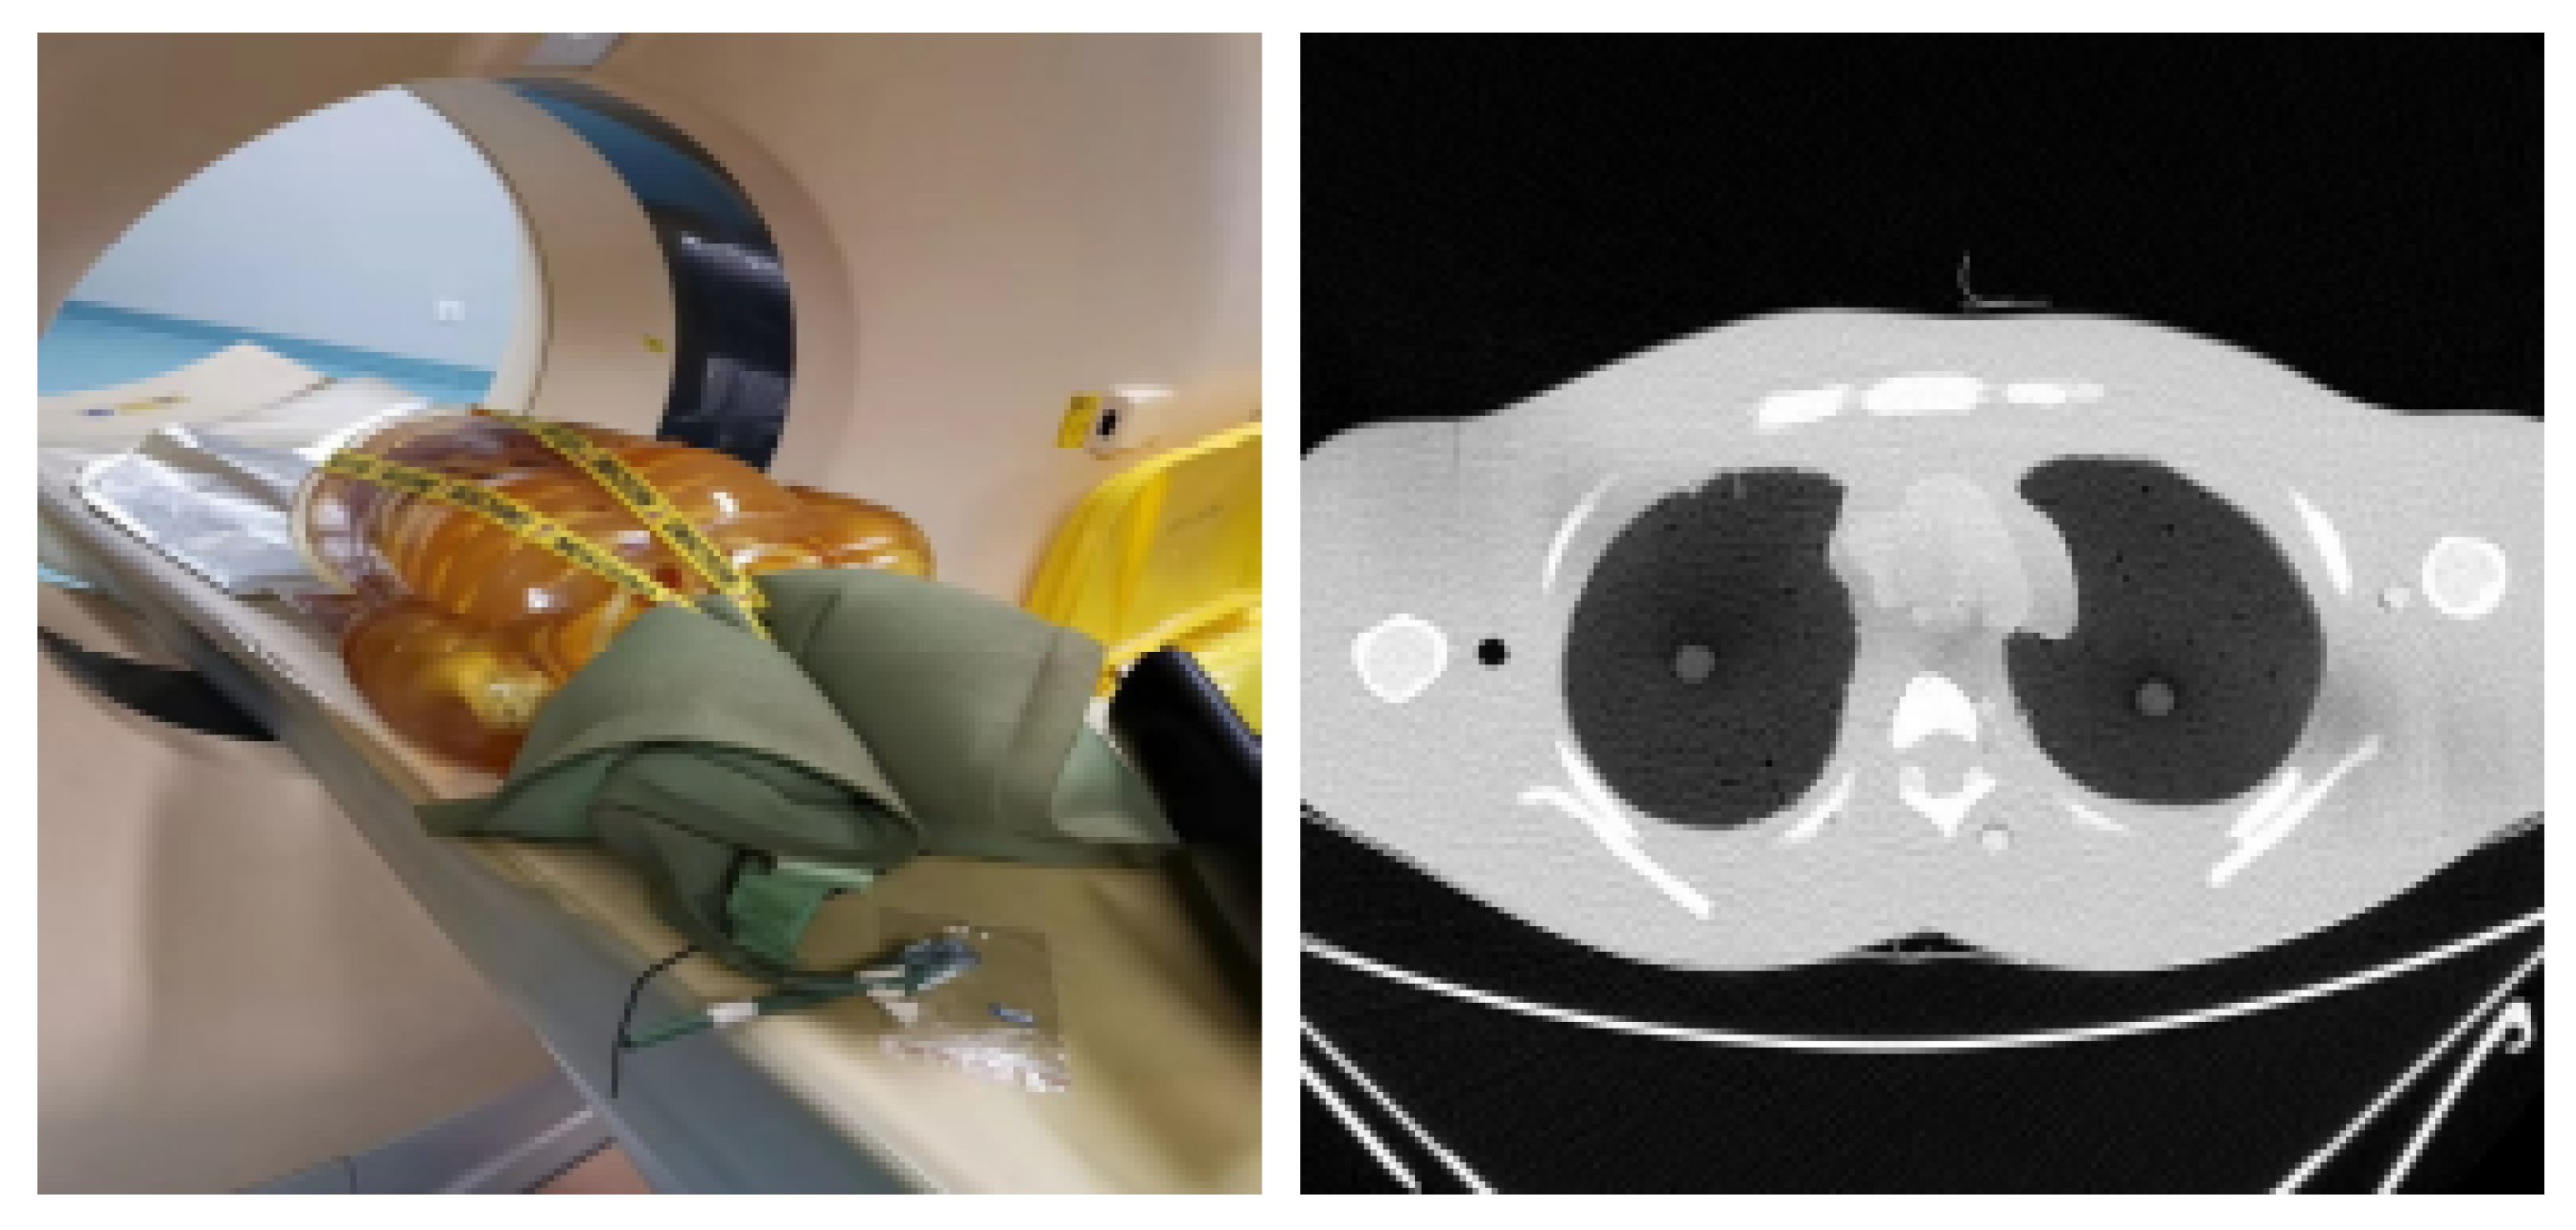

The lung phantom can be seen together with an axial slice in Figure 8.

Figure 8.

Lung phantom placed in CT scanner and a single axial slice.